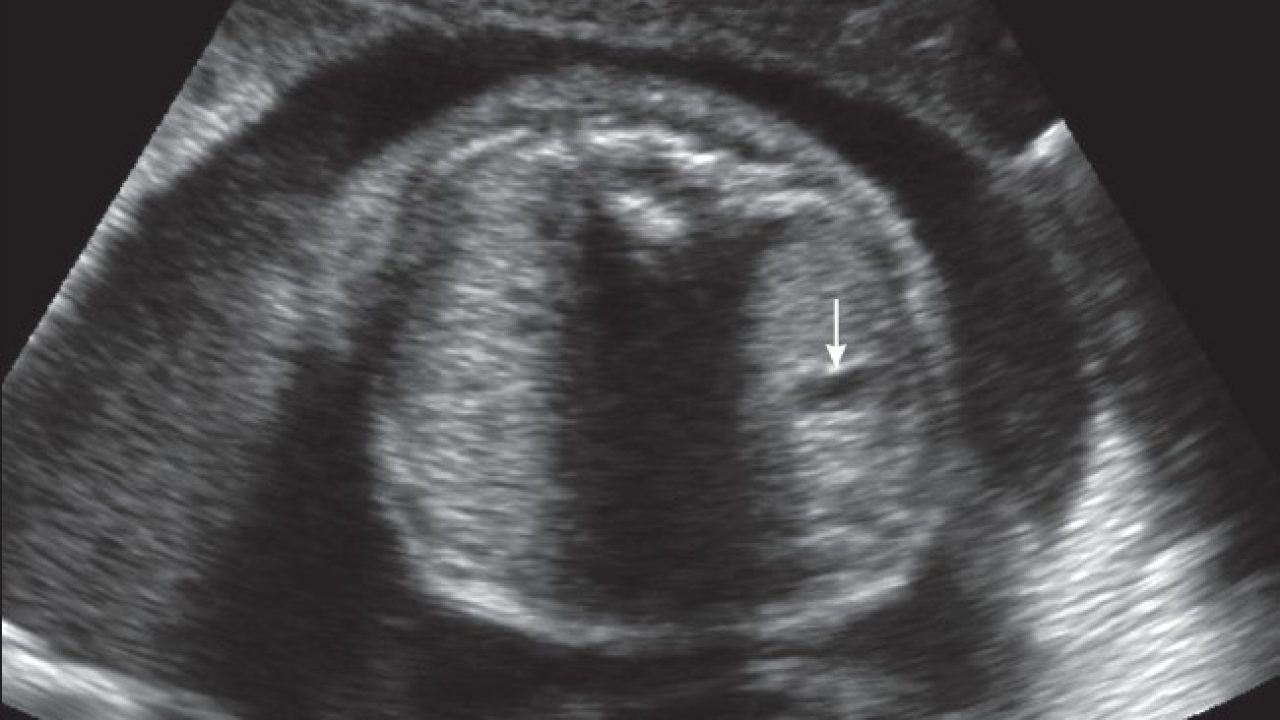

Mengenal Kehamilan Kosong atau Blighted Ovum (BO) - Bidanku.com

Mengenal Kehamilan Kosong atau Blighted Ovum (BO) - Bidanku.com

Mengetahui Tanda-Tanda Kehamilan Kosong - Bidanku.com

Mengetahui Tanda-Tanda Kehamilan Kosong - Bidanku.com

Blighted Ovum

Blighted Ovum